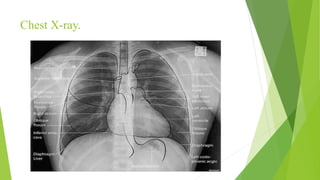

Chest X-ray.